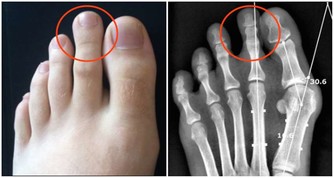

超聲科醫師檢查發現其右側陰囊空虛,右側腹股溝內可見大小約2*2*1cm的類睾丸迴聲,診斷考慮:隱睾症。

超聲科劉友員主任醫師解釋,“蛋蛋”不在陰囊裡就是俗稱的“隱睾症”。

隱睾,是指睾丸在正常發育過程中未下降或下降不全至陰囊,陰囊內沒有睾丸或只有一側有睾丸。

正常睾丸大小約4*3*2cm,位於陰囊內,

陰囊是最適合睾丸生長發育的場所,陰囊內溫度比體溫低1° C-2°C,有利於睾丸產生精子。

而隱睾患者睾丸未進入陰囊,長期留在腹腔和腹股溝管內,這些部分局部溫度高,

可導致睾丸生精細胞損害,影響精子的產生和生存,易導致不育。

此外隱睾由於生長環境改變以及發育上在障礙,容易發生惡變。